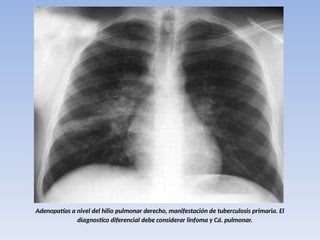

TBC PRIMARIA :

PRESENTACIÓN GANGLIONAR :

• las adenopatías es prácticamente

patognomónica de la fase primaria de la

enfermedad, (90%)

• el grupo mas frecuentemente afectado es el

traqueo bronquial derecho.

• La combinación de una lesión neumónica

lobar con adenopatías es muy típica de

tuberculosis (complejo primario)

Adenopatías a nivel del hilio pulmonar derecho, manifestación de tuberculosis primaria. El

diagnostico diferencial debe considerar linfoma y Cá. pulmonar.